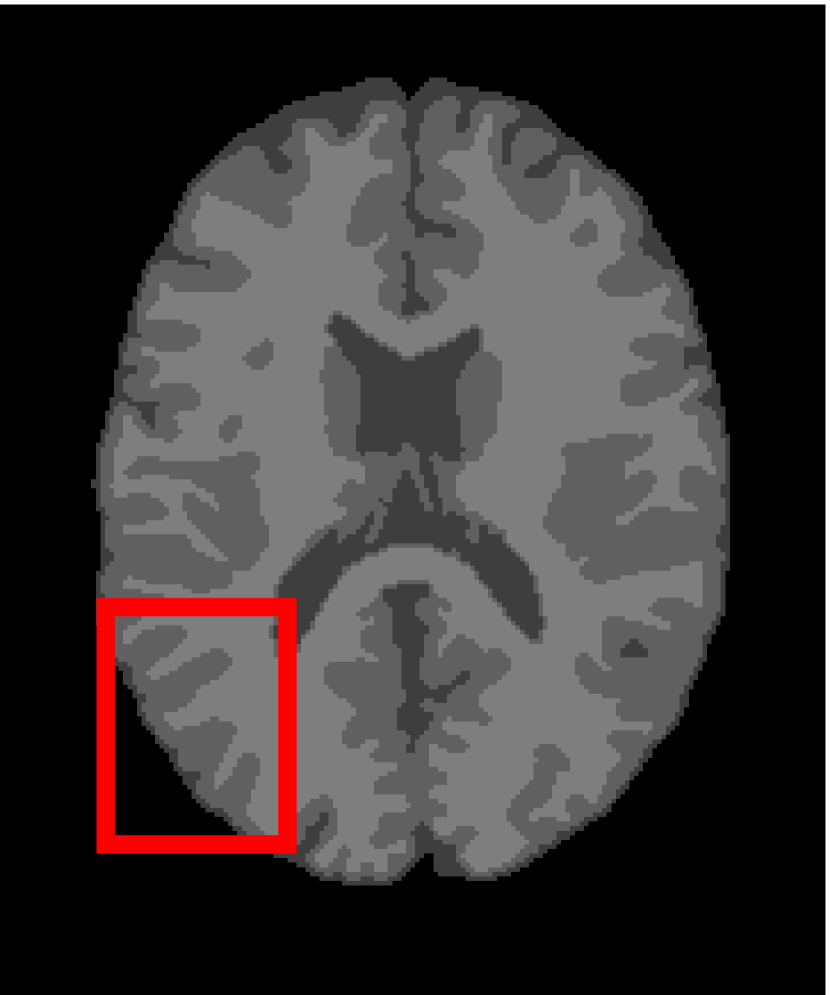

4.4.2 Results on Medical Images

Next, we representatively segment five medical images from BrianWeb. They are represented as five slices in the axial plane with a sequence of 70, 80, 90, 100 and 110, which are generated by T1 modality with slice thickness of 1mm resolution, 9% noise and 20% intensity non-uniformity. Here, we set c=4𝑐4c=4 for all cases. The comparison between WRFCM and its peers are shown in Fig. 9 and Table II. The best values are in bold.

Figure 9: Segmentation results on five medical images. The parameter: ϕ=5.35italic-ϕ5.35\phi=5.35. From top to bottom: noisy images, ground truth, and results of FCM_S1, FCM_S2, FLICM, KWFLICM, FRFCM, WFCM, DSFCM_N, and WRFCM.

TABLE II: Segmentation performance (%) on medical images in BrianWeb

Algorithm Fig. 9 column 1 Fig. 9 column 2 Fig. 9 column 3 Fig. 9 column 4 Fig. 9 column 5

SA SDS MCC SA SDS MCC SA SDS MCC SA SDS MCC SA SDS MCC

FCM_S1 75.756 97.852 96.225 75.026 98.109 96.656 79.792 98.452 97.334 81.887 98.614 97.680 81.869 94.254 90.947

FCM_S2 75.769 98.119 96.664 74.970 98.176 96.765 79.886 98.458 97.338 82.073 98.625 97.695 81.788 98.223 97.195

FLICM 74.998 98.070 96.568 74.185 98.122 96.660 79.099 98.515 97.432 81.447 98.627 97.691 81.668 98.273 97.260

KWFLICM 74.840 98.259 96.878 73.839 97.860 96.190 79.560 98.453 97.316 81.887 98.482 97.443 81.370 98.297 97.286

FRFCM 75.853 97.620 95.775 75.514 97.660 95.830 80.283 98.278 97.013 81.852 98.319 97.171 81.666 98.079 96.945

WFCM 75.507 97.124 94.957 74.471 97.213 95.045 79.316 97.845 96.283 81.358 97.546 95.211 81.452 95.247 92.501

DSFCM_N 76.400 92.325 86.262 75.288 91.574 85.095 79.861 97.678 95.996 81.831 93.304 88.829 81.750 94.302 91.024

WRFCM 82.317 98.966 98.147 82.141 98.298 96.970 83.914 98.963 98.202 83.533 99.170 98.603 84.615 98.429 97.511

By a view of the marked red square in Fig. 9, we find that FCM_S1, FCM_S2, FLICM, KWFLICM and DSFCM_N are vulnerable to noise and intensity non-uniformity. They give rise to the change of topological shapes to some extent. Unlike them, FRFCM and WFCM achieve sufficient noise removal. However, they produce overly smooth contours. Compared with its seven peers, WRFCM can not only suppress noise adequately but also acquire accurate contours. Moreover, it yields the visual result closer to ground truth than its peers. As Table II shows, WRFCM obtains optimal SA, SDS and MCC results for all five medical images. As a conclusion, it outperforms its peers visually and quantitatively.